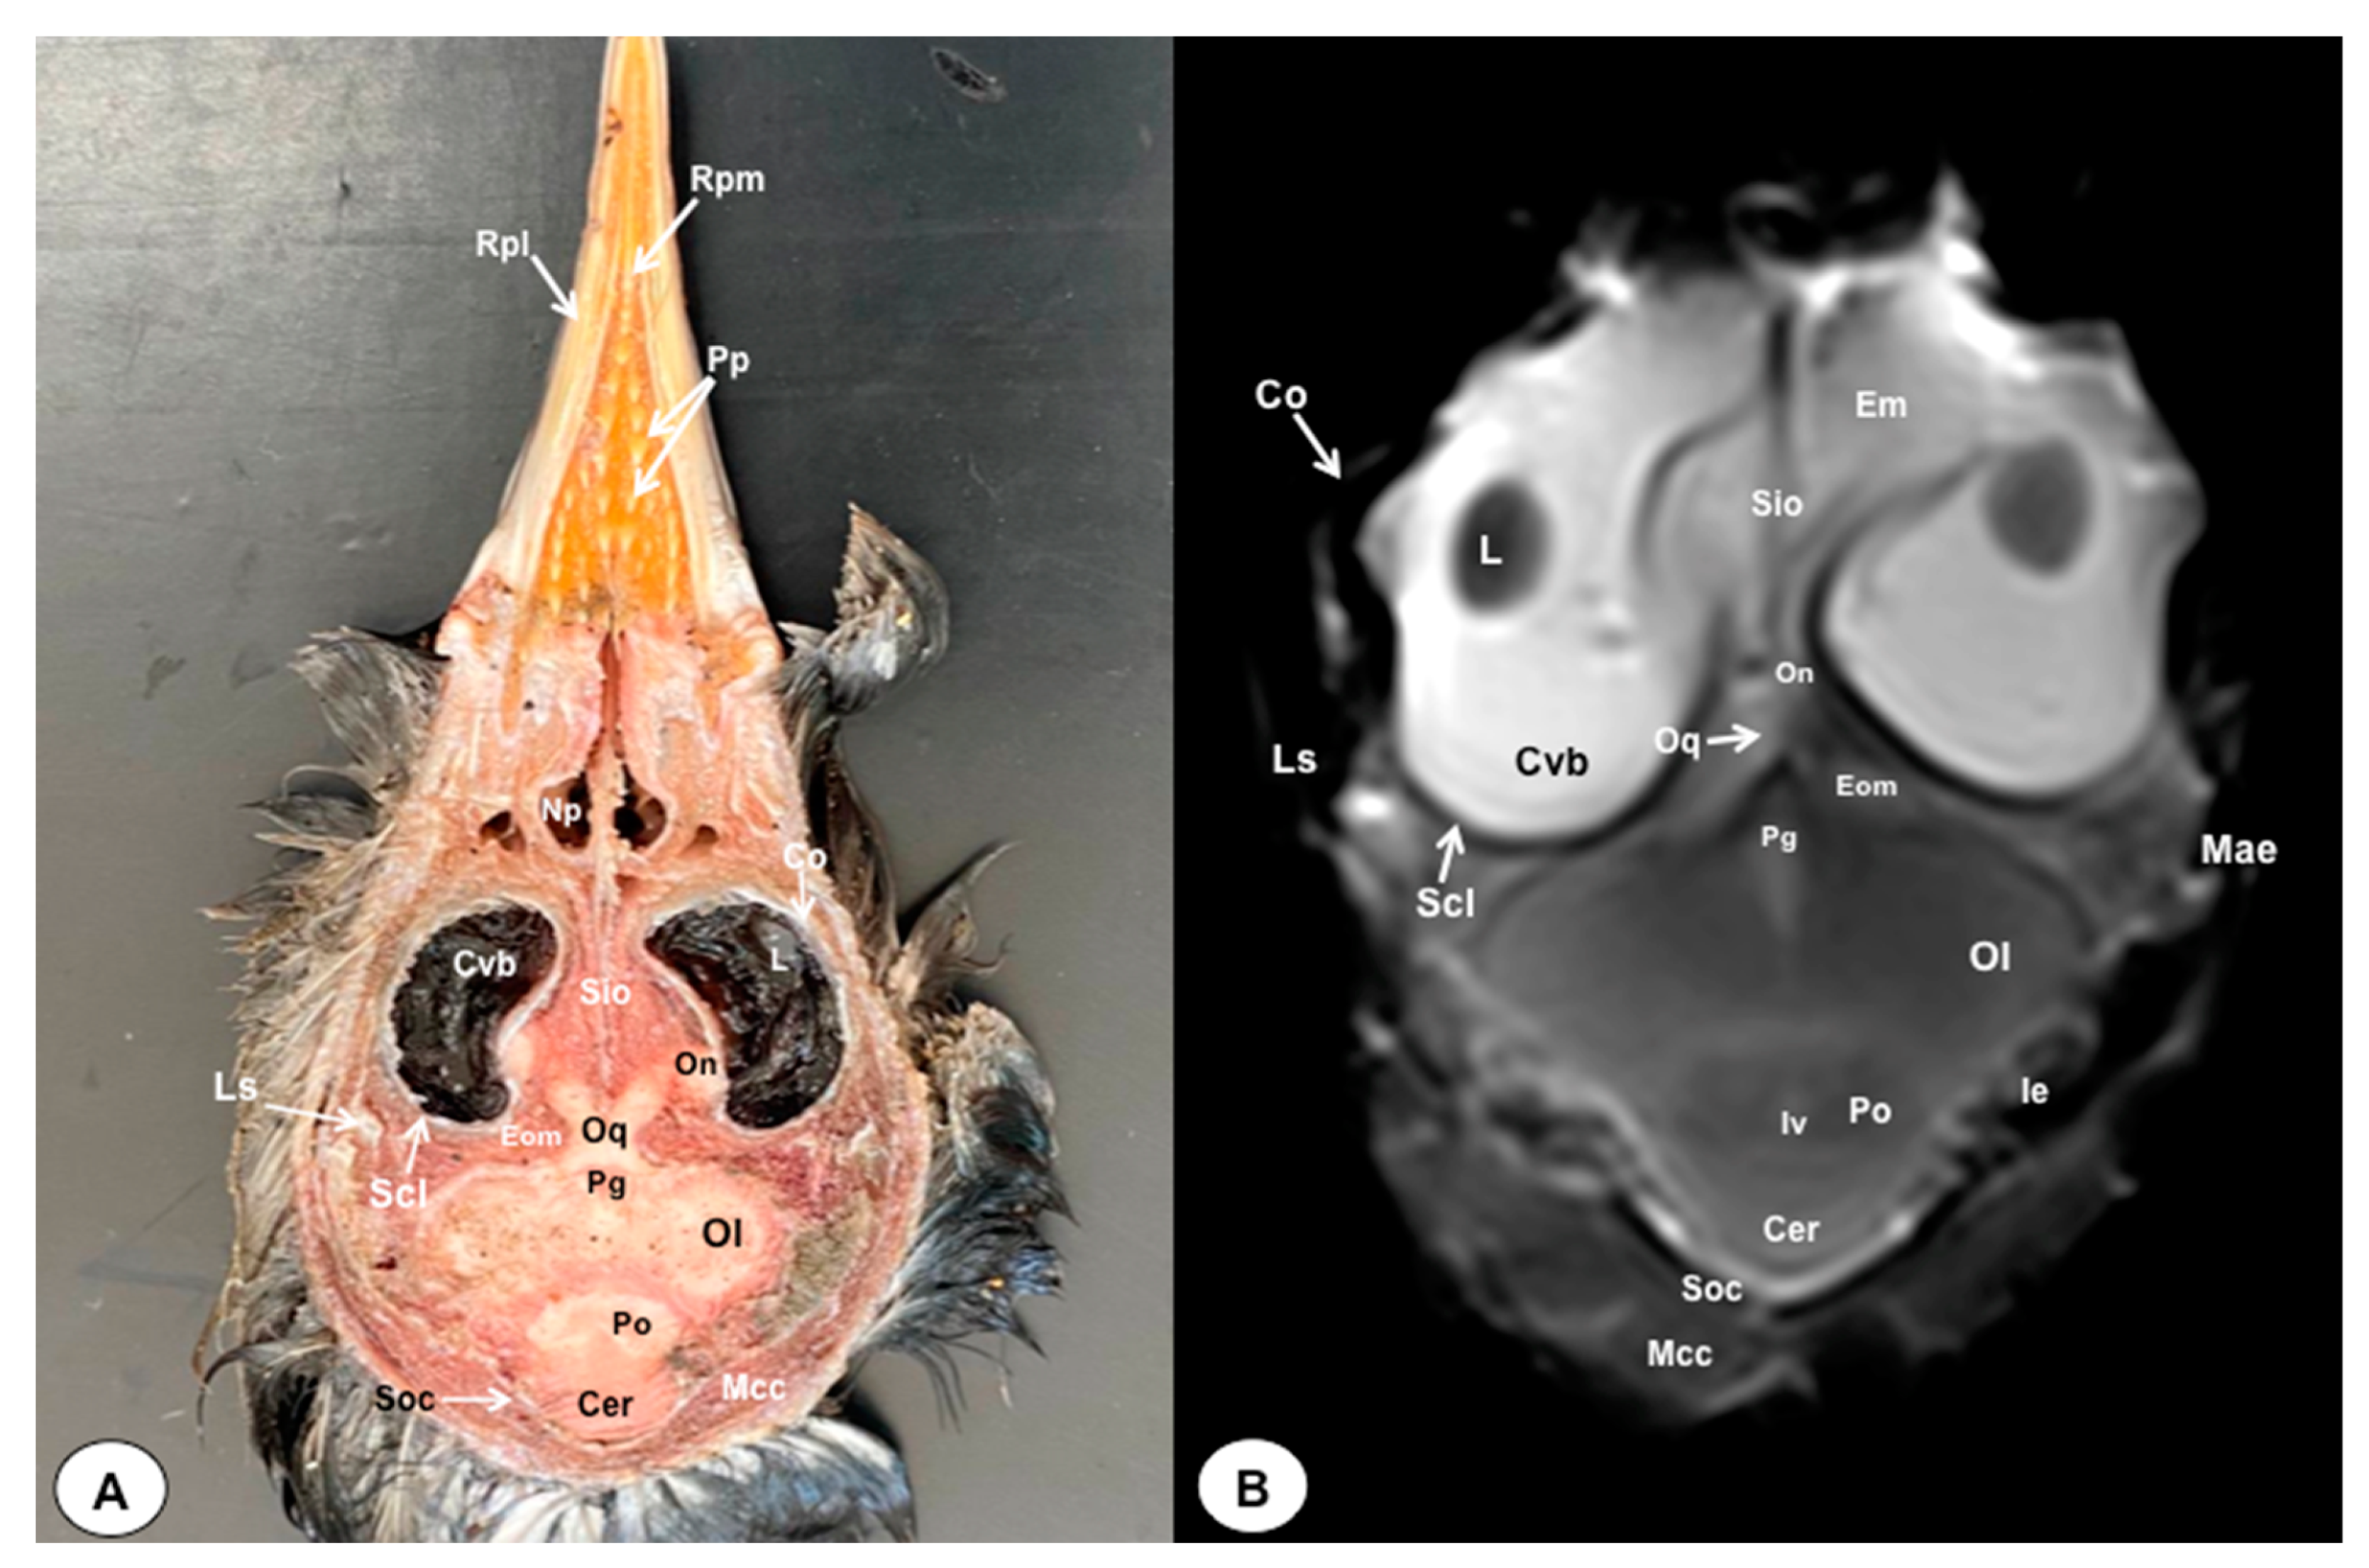

3.1. Anatomical Sections

3.2. Magnetic Resonance Imaging (MRI)